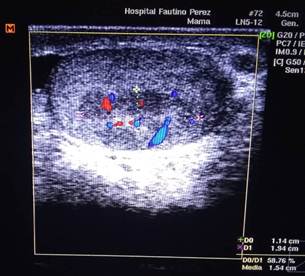

Scrotal Doppler ultrasound (Figure 1): showed a mixed, hypoechoic tumor mass located in the front part and upper pole of the left testicle, measuring 10 × 8 mm, with cystic areas inside and tiny calcifications. Color Doppler study showed increased internal blood flow (highly vascular), a pattern suggestive of germ cell tumor (Figure 2). On cross-sectional imaging, the solid nature of the lesion was seen, with irregular edges and no posterior acoustic shadow (Figure 3).

Figure 2: Color Doppler ultrasound, same patient. The mass shows increased internal blood flow (highly vascular), a pattern suggestive of germ cell tumor.